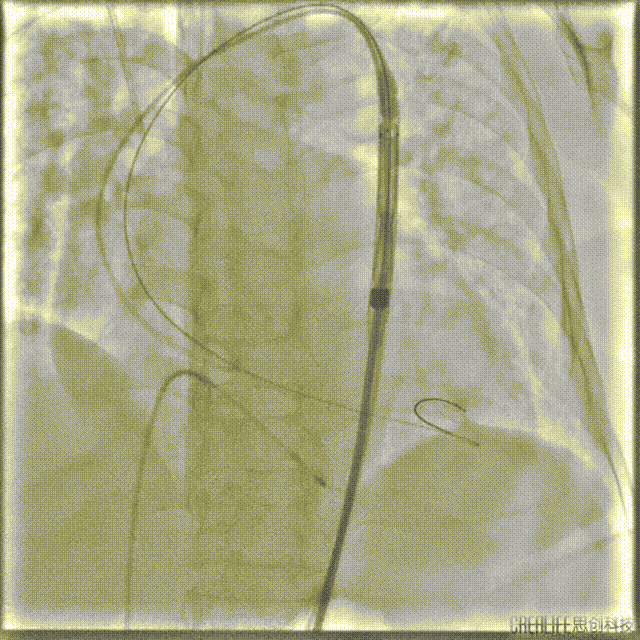

导丝跨瓣

选择22mm球囊进行预扩,结果显示具有明显腰征,无瓣周反流,遂即选择TaurusElite 26mm瓣膜,凭借其优异的柔顺性,轻松完成过弓。

球囊预扩

TaurusElite顺利过弓